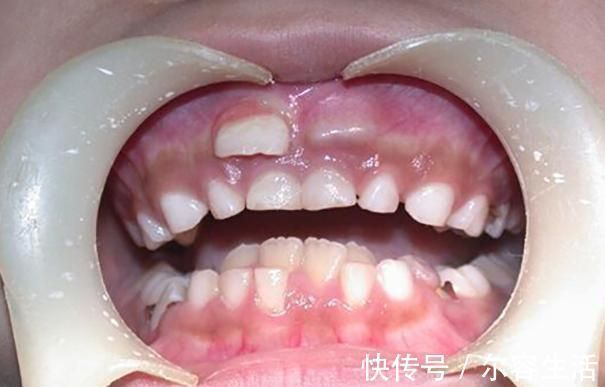

什么叫做“双排牙”?其实双排牙的主要原因是在换牙期,乳牙滞留,导致恒牙生长受阻,最后恒牙和乳牙并排而立。形成双排牙的主因有很多,糖果的关系并不大,和家长的喂养习惯相关。

一、孩子长出双排牙,一家人跟着着急何丽的女儿今年已经六岁多了,正值换牙时期,可是门牙始终都不松动,父母也没有太在意。可有一天女儿告诉妈妈,自己的门牙里面有两个硬硬的东西。因为门牙没有松动,恒牙没地方长,只能从旁边长出来了。何丽还是没有在意,等着孩子这几天门牙的松动,然后再给孩子拔掉。可是等了近一个多月,孩子的牙齿还是没有松动的迹象。于是何丽察觉到有一些不对劲了,就带着孩子去看了医生。医生说这两年双排牙的孩子越来越多,大部分都是因为饮食习惯不规范造成。

1. 孩子从小不吃硬的食物造成双排牙的极大可能,都是和饮食习惯有关,孩子在添加辅食开始,就是吃泥状食物。随后应该慢慢过渡到颗粒状食物,然后是小块状食物,最后孩子就能独立啃咬完整的食物。但是很多父母担心孩子不吃饭,于是都视线将食物处理好,孩子基本上接触不到稍硬的食材。最后导致乳牙得不到锻炼,就没有松动的迹象。2. 孩子自身的疾病还有些孩子是因为先天性的疾病,或者是继承恒牙出牙无力等等,这些都需要提前看医生,如果乳牙滞留的时间太长,就可以让医生拔出乳牙,让恒牙顺利长出来。

二、长出双排牙的危害1. 影响孩子外貌双排牙的主要危害,还是会影响孩子的外貌长相,孩子的恒牙会伴随一辈子,因为乳牙的滞留,长歪或者长坏了,孩子的整提外貌就会有影响,可能后期还需要花钱矫正,受罪又花钱。而且牙齿长歪了,孩子面部也会发生改变。2. 影响孩子进食双排牙会影响孩子的近视,由于畸形的牙缝存在,孩子咀嚼食物的时候,会产生不适感。而且两张牙齿并立而存,牙龈也会感到不舒服。如果孩子的双排牙影响了进食,那么孩子身体营养就无法跟上了。

3. 影响孩子恒牙生长乳牙滞留最主要的问题就是影响恒牙的生长,如果乳牙长期不松动脱落,孩子也不去看医生,最后可能会造成恒牙的损伤。将来即使乳牙脱落了,恒牙的损伤也无法避免了。4. 影响口腔清洁如果孩子已经长了双排牙,由于难以清洁,孩子肯定会有食物在牙缝里,造成口臭。孩子有口臭,张口说话其他人就能闻到,同学们可能会笑话孩子。